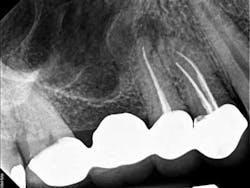

A 50-year-old male presented to my office on referral from his general dentist for evaluation of a large, periapical radiolucency relating to Nos. 4 and 5. Appropriate bitewing and peri-apical radiographs were taken (Fig. 1) for initial evaluation. After all clinical testing was performed, the recommendation was made to take a narrow-field CBCT image of teeth Nos. 4 and 5 (Figs. 2 and 3). The axial view reveals an untreated buccal canal on tooth No. 4 and potential separated instruments in both the buccal and palatal canal space of No. 5. Tooth No. 5 (Fig. 3) shows a short fill, meaning the entire canal space may not have been properly shaped and cleaned. With the three-dimensional images, we now have a better understanding of why these teeth present with post-treatment disease. This information is extremely important when discussing etiology and prognosis with our patients. It will also financially benefit the patient to maintain his existing fixed prosthesis with conservative retreatment of Nos. 4 and 5, knowing that we should have a high degree of long-term success seeing a clear etiology of the post-treatment disease.